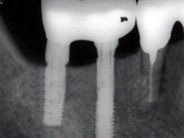

右下顎にインプラントを入れました。

入れ歯の必要がなくなりました。8年経過しています。

人生が変わるほどよく咬めるようになりました。

8年間全く異常を認めません。